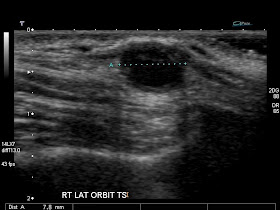

7mm Nodule Lung Biopsy

I biopsied this 7mm nodule. The result came back as "Normal Lung Tissue". This patient had a lobectomy -- result "Well differentiated adenocarcinoma".